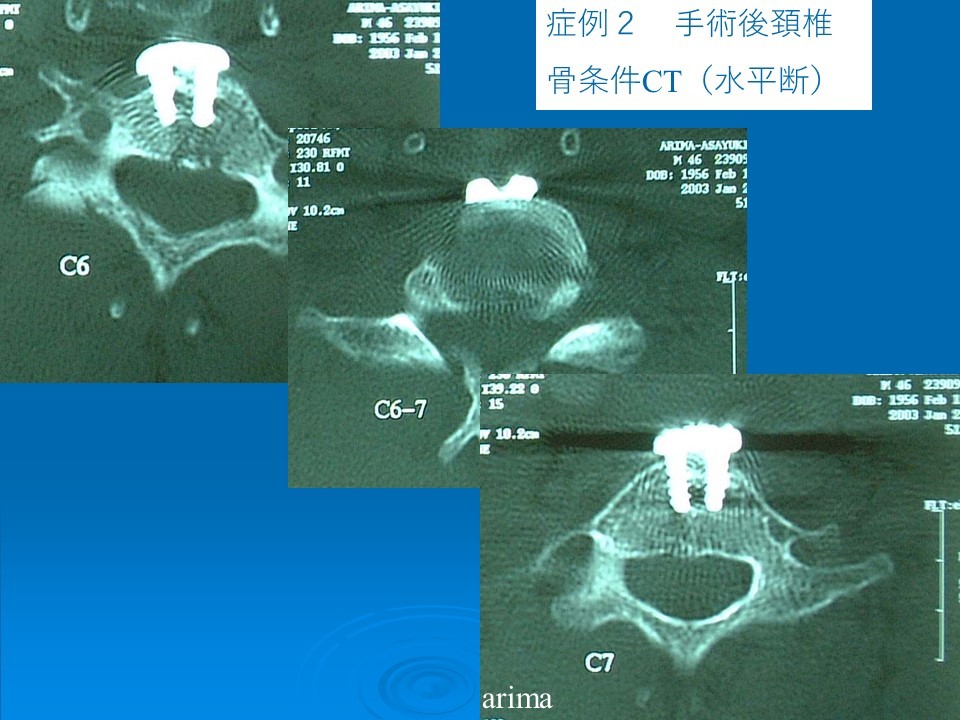

頸椎症に対する手術法は大きく分けて前方よりのアプローチと後方からの椎弓形成術に分けられます。前方アプローチは頚椎症の病態を考えると後方アプローチより理にかなった術式であり、自然な前彎をたもつことができます。顕微鏡下で椎間板を摘出し、椎間板面の椎体をドリルで薄く削開し、さらに後方骨棘をドリルで削除し、自家骨(腸骨という腰の前外側の骨をとります)もしくは人工骨(アパセラム、チタンケージ、プラスチックケージ等)を使用して椎体間固定を行います。